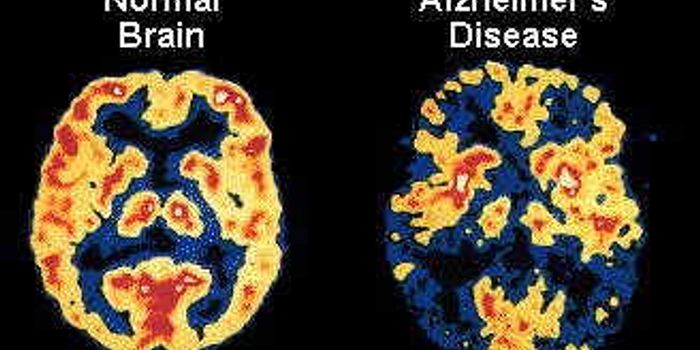

NOV 13, 2017InfographicsIn 1983, President Ronald Reagan designated November as National Alzheimer’s Disease Awareness Month. As it turns ...